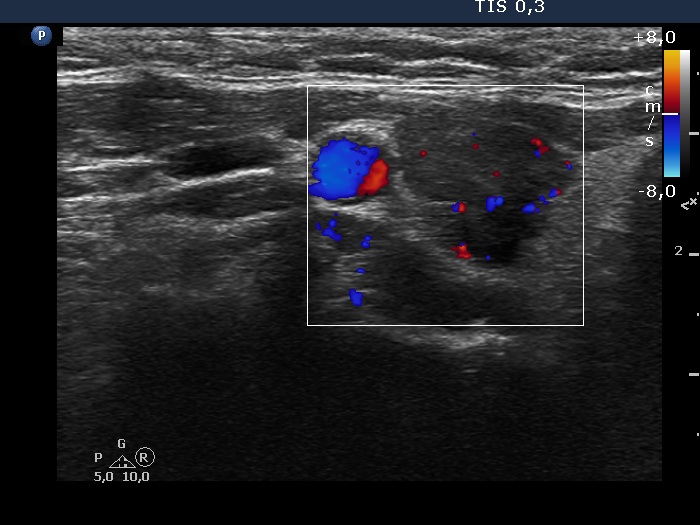

The borders of the nodule - case 2068

4 years after the sclerotherapy (ultrasonographic picture 3)

Right lobe, transverse view, color Doppler mode. The vascularization is normal or a bit increased.